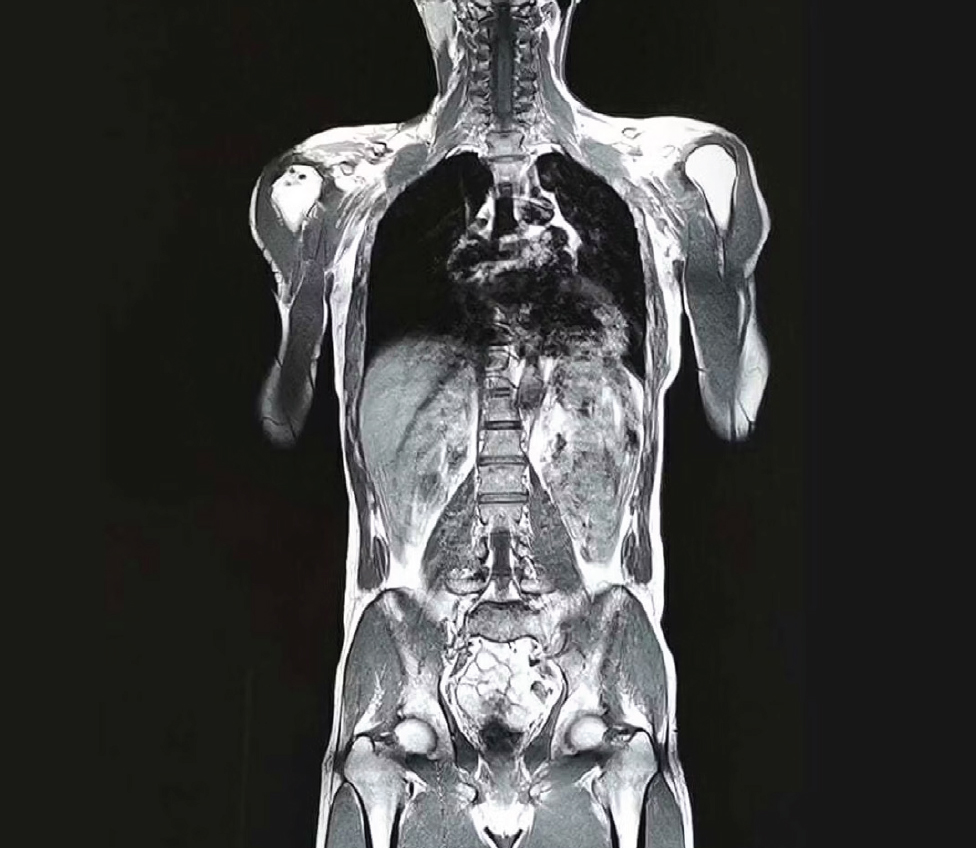

WHOLE BODY IMAGING (WBI)

An MRI is a safe and painless test that uses a powerful magnet, radio waves, and a computer to create detailed pictures of the inside of your body.

Whole body imaging screens the body and has the ability to detect hundreds of different conditions including many types of early-stage cancer, multiple sclerosis, brain aneurysms, narrowing of the arteries, ischemic injury, vascular malformations, various metabolic disorders, disc herniations, endometriosis, neurodegenerative disorders and spinal degeneration. Mayfair whole body scans will be interpreted and reported by sub-specialty-trained radiologists with extensive oncologic-imaging interpretation experience.

This non-invasive, multi-dimensional screening view of the body using magnetic resonance imaging (MRI) can be used to evaluate possible conditions before they become a concern, allowing you to better manage your health. State-of-the-art whole body imaging may lead to early diagnosis, allowing you to achieve peace of mind and better manage your health.

Whole body imaging (WBI) takes approximately one hour and evaluates:

• The brain, including its major blood vessels.

• The spine and spinal cord.

• The major organs of the body, including the salivary and thyroid glands, lymphatic system, liver, gallbladder, biliary system, pancreas, spleen, adrenal glands, kidneys, bladder, uterus, ovaries, prostate and testes.

• The lungs and bowel are not optimally assessed with MRI but supplemental low-dose CT of the lungs and colon can be obtained as an add-on.

• Dedicated evaluation of the major joints of the body is also available as an add-on.